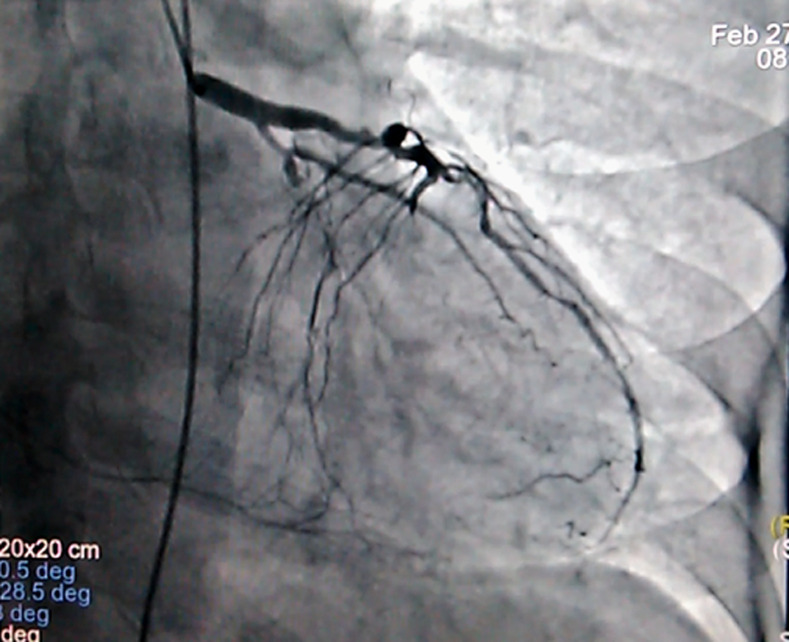

Abnormalities in the aVR lead would provide useful information on the risk of coronary heart disease. This clinical case is an illustration. Indeed, this is a 60-year-old patient, an active smoker and a former type 2 diabetic who presented with angina-like chest pain with a positive stress test. The initial electrocardiogram showed a discreet elevation of the ST segment and an aVR necrosis Q wave with mirror signs in the inferior territory. An ischemic heart disease with altered ventricular ejection fraction was objectified. The diagnostic coronary angiography objectified a multi-vessel coronary lesion. Ultimately, the aVR lead provides valuable clinical information and argues for special attention to this often forgotten lead.